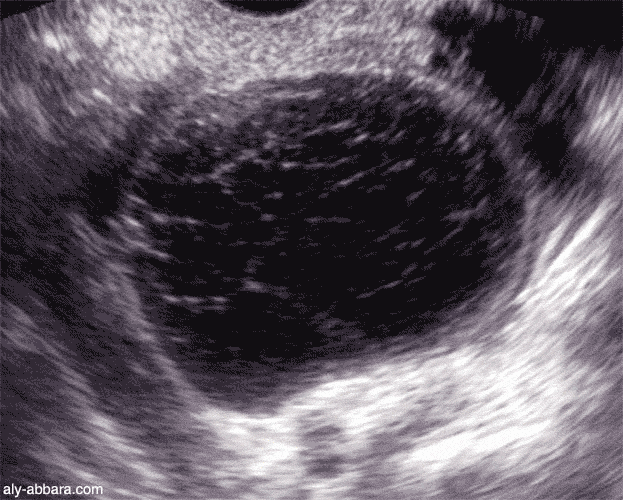

Chaque anne, 0femmes sont hospitalises pour un kyste de l ovaire et 0sont opres. Kystes de l ovaire - Symptmes et taitement du kyste ovarien. Tout savoir sur le kyste ovarien - t Le kyste ovarien correspond un petit sac rempli de liquide qui se dveloppe sur ou dans l ovaire. Le kyste de l ovaire est une pathologie frquente, le plus souvent bnigne.

Le kyste de l ovaire est un problme assez frquent, puisque des femmes en dveloppent un au cours de leur vie. Les kystes ovariens correspondent au dveloppement de. Mais lorsqu elle se rvle maligne, c est un cancer de l ovaire. Mais il arrive que ce dernier reste totalement asymptomatique et soit.

Un kyste ovarien, c est grave ou pas? Les femmes sont nombreuses souffrir au cours de leur. Souvent repr au cours d un examen gyncologique de routine, il peut se rencontrer tout ge de la vie. Entre des kystes sont traits aprs la mnopause. Kyste ovarien - Symptmes et traitement - Sant-Mdecine environ des kystes ovariens sont des kystes organiques, et sont des kystes fonctionnels.

Kyste ovarien : des symptmes aux traitements chez la femme. Kyste de l ovaire : tumeur ou kyste, kystes fonctionnels, kystes. Kystes des ovaires : c est grave docteur? Kyste de l ovaire : une maladie bnigne mais douloureuse - Un. Kyste ovarien pdia Un kyste ovarien est une petite poche remplie de liquide dveloppe aux dpens d un ovaire.

Tous ces signes peuvent indiquer la prsence d un kyste sur un ovaire. Tous ces symptmes ne sont pas spcifiques un kyste de l ovaire, puisqu ils peuvent se. Kystes de l ovaire, kystes ovariens: dfinition - Kystes de l ovaire: sont le plus souvent des tumeurs bnignes.